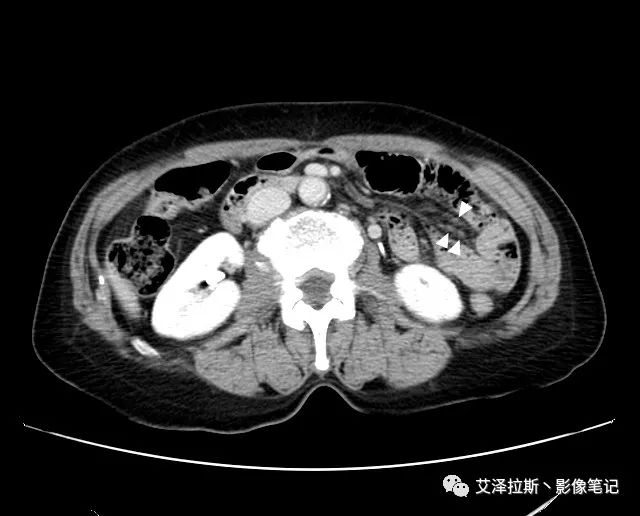

圖1 平掃+增強(qiáng)各期

【影像所見】 胃竇部狹窄,胃壁環(huán)形增厚,小彎側(cè)見一巨大潰瘍,周圍伴“環(huán)堤征”,漿膜面不完整,胃周脂肪見網(wǎng)格狀條索影,病灶與肝臟左葉、胰腺鉤突脂肪間隙消失,增強(qiáng)掃描病灶明顯強(qiáng)化。引流區(qū)內(nèi)約15個區(qū)域淋巴結(jié)受累。

【診斷意見】 胃竇部胃癌(T4N3期) 該病例腫塊突破漿膜層,與肝臟左葉、胰腺鉤突分界不清,脂肪界面消失,定為T4期; 受累及的淋巴結(jié)為15個區(qū)域,定為N3; 有無遠(yuǎn)處轉(zhuǎn)移尚不明確,所以M期暫時無法確定。